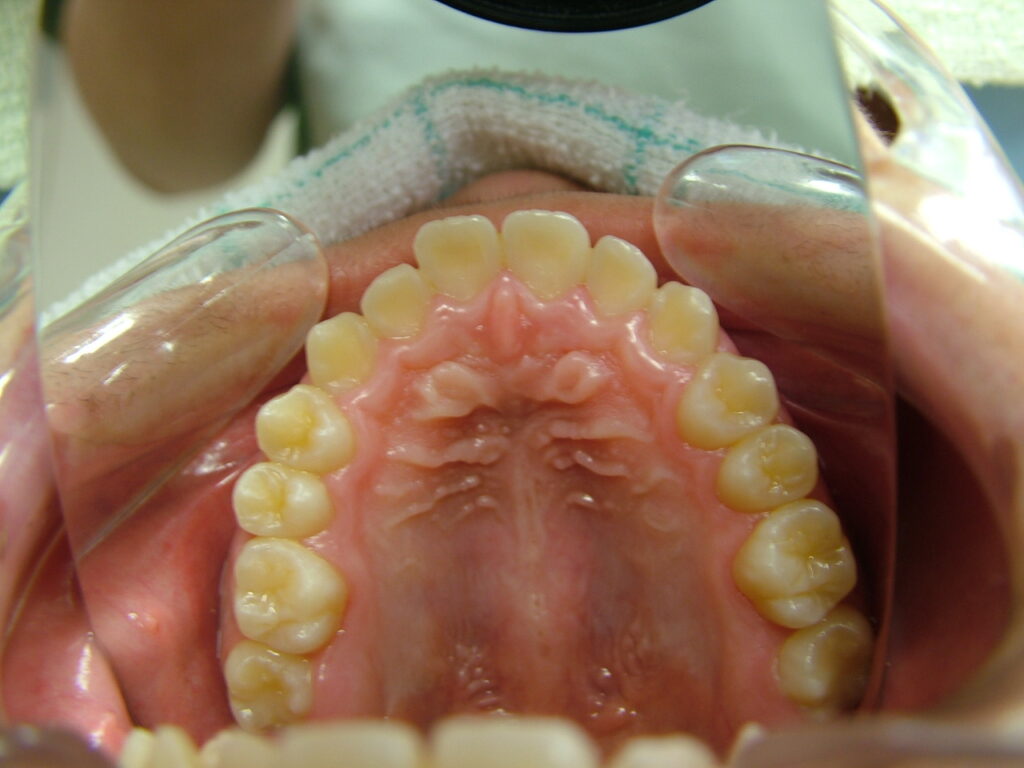

治療前

- 診断:1級咬合、左偏位、下永久歯(犬歯)萌出スペース不足

- 治療方針:非抜歯で行う。虫歯予防(フッ素)、歯磨き指導、舌位の改善、上下拡大床+補助断線→マウスピース矯正→下親知らずの抜歯、保定→メンテナンス